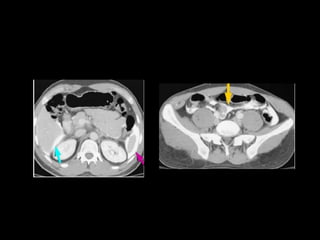

Arteriografía S-89 Y E-91

TAC S-95 Y E-97

•

GRADO ll

GRADO lll

GRADO IV